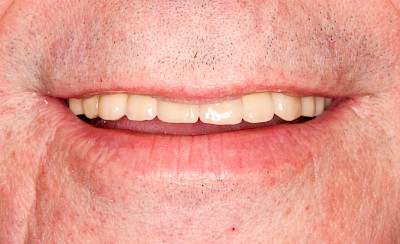

Fehlen einzelne Zähne und die Nachbarzähne sind unbeschadet oder gut zahnärztlich versorgt, werden immer häufiger Implantate gewählt um die Lücken zu schließen. Auch bei größeren oder verteilten Lücken, wenn keine herausnehmbare Prothese gewünscht ist, werden Implantate für Kronen- bzw. Brückenversorgungen gesetzt. In Einzelfällen entscheiden sich sogar zahnlose Patienten für eine festsitzende Versorgung auf Implantaten.

Bei herausnehmbaren Prothesen werden Implantate eingesetzt, um den Halt und den Tragekomfort der Prothesen zu verbessern. Dazu kommen verschiedene Verbindungselemente zum Einsatz: